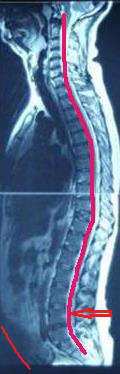

대표적으로 비만 체형을 들 수 있는데 비만으로 인해 복부지방이 과하게 축적되어 배가 나오게 되면 배만 나오는 것이 아니라 척추의 만곡의 지나치게 앞으로 이동하게 됩니다. 이를 과전만이라고 표현하며 정상적인 60도의 척추만곡 각도보다 더 작게 됩니다.

이렇게 되면 중력에 저항하여 우리 몸을 지탱하는 역할을 척추 분절 골고루 할 수 없게 되어 어느 특정한 분절에서 몸무게를 떠 안게 됩니다. 따라서 주변 조직인 디스크, 인대, 근육 등이 부담을 받게 되고 점점 손상이 일어나게 됩니다. 또한 정상적이고 탄력적인 척추의 움직임을 보일 수 없게 되어 특정분절의 움직임이 과도하게 되거나 움직임이 줄어들게 되면서 효과적인 움직임을 보이기 어렵습니다.